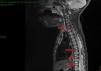

Niña de 2 años de edad, sin antecedentes personales o familiares de interés. Acudió al servicio de dermatología por presentar varias placas ulceradas y cubiertas de escamocostras en cuero cabelludo desde el nacimiento (fig. 1). No lo había tratado con nada. En la exploración destacaba la existencia de una adenopatía de pequeño tamaño en la región cervical posterior. Realizamos una biopsia cutánea y otra de la adenopatía, informadas de histiocitosis de células de Langerhans (HCL). Ante esto, y para descartar compromiso a otro nivel, ampliamos el estudio con una RMN donde se visualizaron múltiples lesiones osteolíticas en varios cuerpos vertebrales (fig. 2). Se diagnosticó de HCL multisistémica. Recibió tratamiento quimioterápico (vinblastina, prednisona y mercaptopurina) logrando remisión completa de la enfermedad. En la actualidad, la paciente está asintomática.